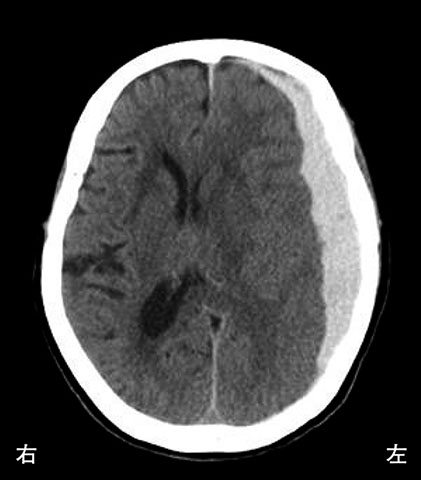

次の文により21・22の問いに答えよ.66歳の女性.右利き.階段から転落.転落直後は意識消失していたが,数分後に意識回復.しばらくの間,意識は清明であったが,1時間後に手足の麻痺が出現し,再び意識が低下して昏睡になった.救急搬送時の頭部CTを下に示す.

解答: 5